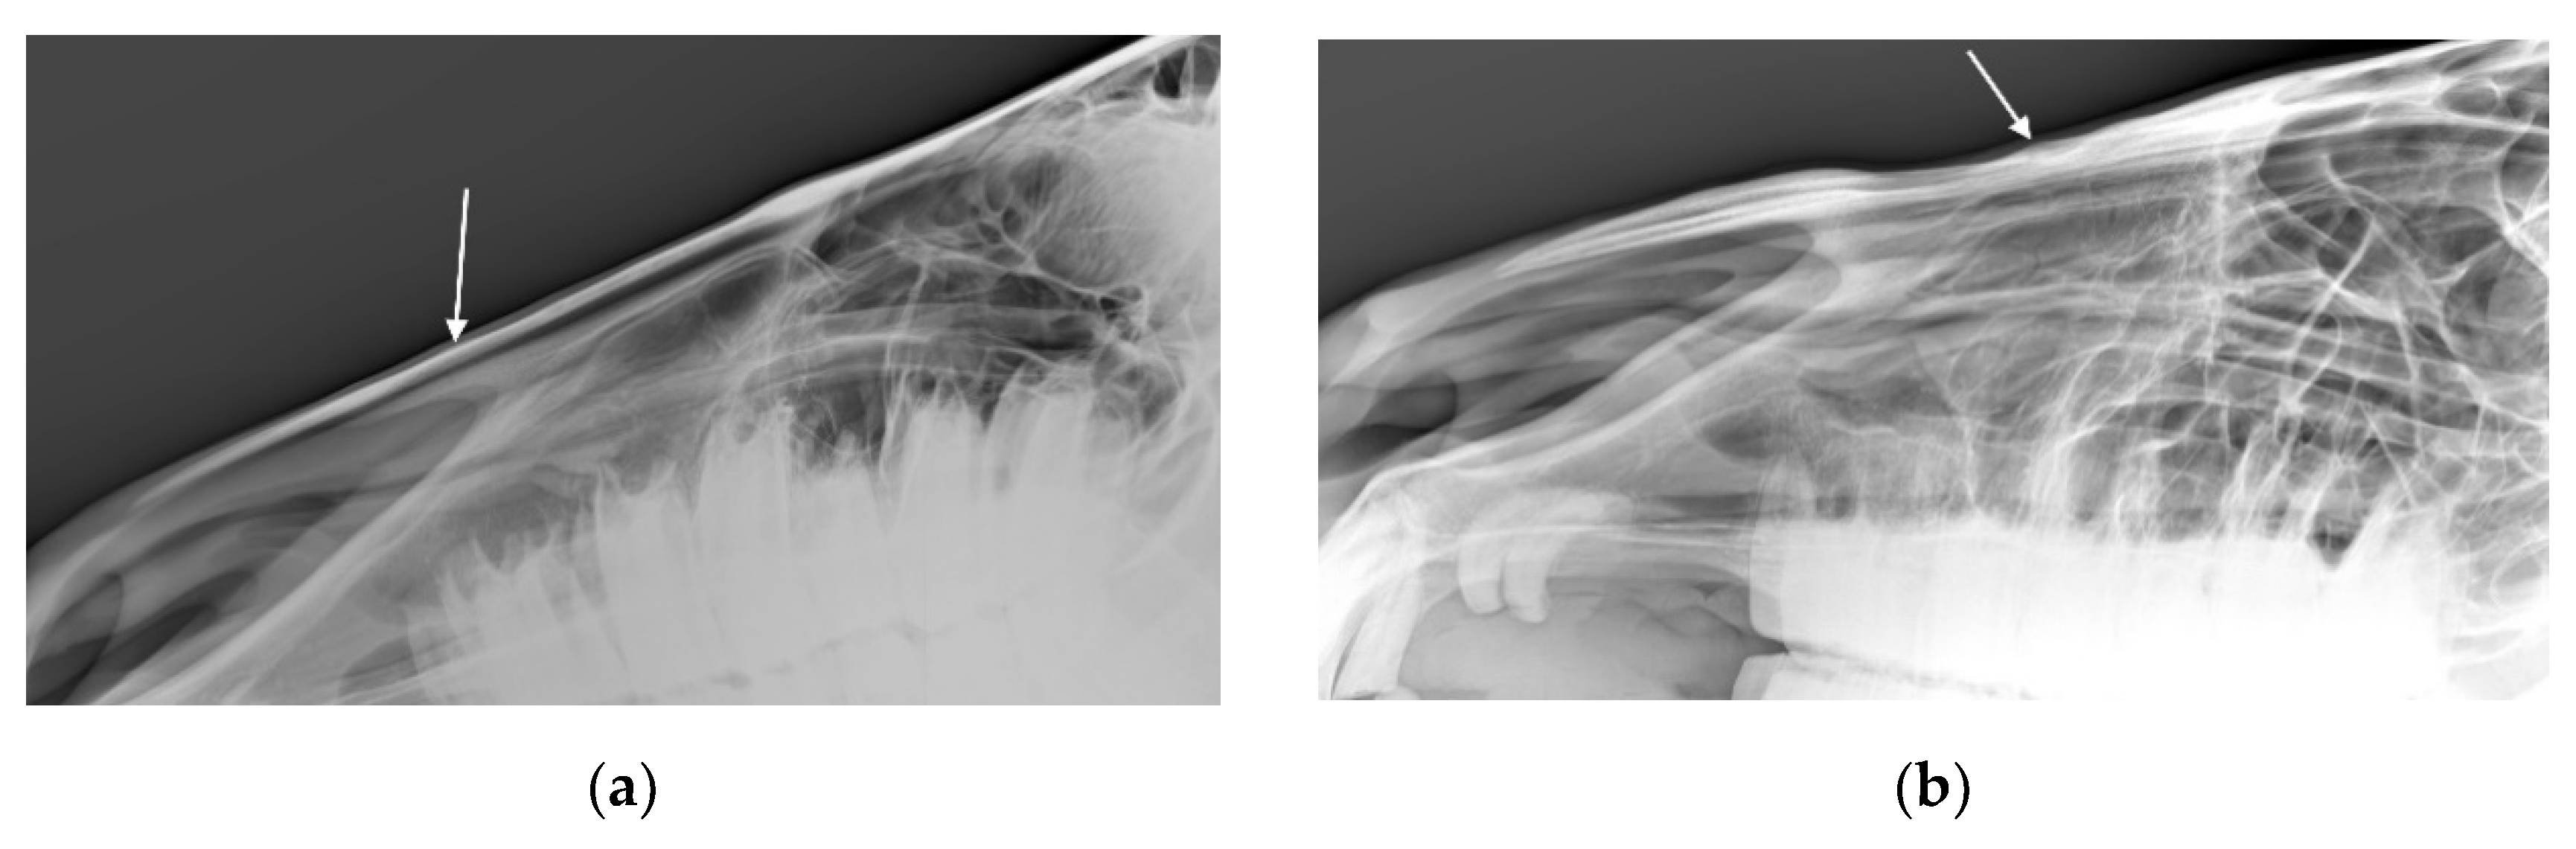

For the 32 horses where the radiologists agreed there was at least one radiographic mandible change, the radiologists agreed about the presence or absence of bone deposition in n = 22 (69%; see Figure 8), the presence or absence of loss of bone homogeneity in n = 25 (78%, see Figure 9), the presence or absence of bone thinning in n = 30 (94%), and the presence or absence of soft tissue swelling in n = 18 (56%). An example of a radiograph showing both bone thinning and bone deposition is shown in Figure 10.

Figure 10. Radiograph showing the nasal bones of a horse in which radiologists (n = 2) agreed there was both bone thinning and bone deposition.